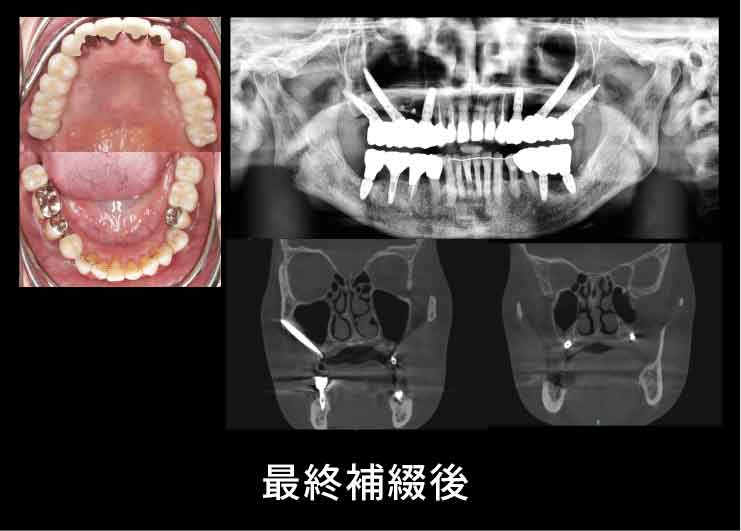

Case3. 65歳女性

歯周病でインプラント、歯が脱離。

上あごの骨が非常に薄く、そのままではインプラントを埋め込むことができないため、Xマークを使用したザイゴマ(頬骨)インプラントおよびプテリゴイド(蝶形骨)インプラントを行ったケース。

ザイゴマインプラント

上あごの骨が十分にない場合には、強固な頬骨に長めのインプラントを埋め込むことで、しっかりとインプラントを固定することができます。

X-ガイドにより、正確な手術が可能です。

X-ガイドにより、正確な手術が可能です。

プテリゴイド(蝶形骨)インプラント

骨移植など、サイナスリフトを避けた手術を行えます。X-ガイドにより、正確な手術が可能です。